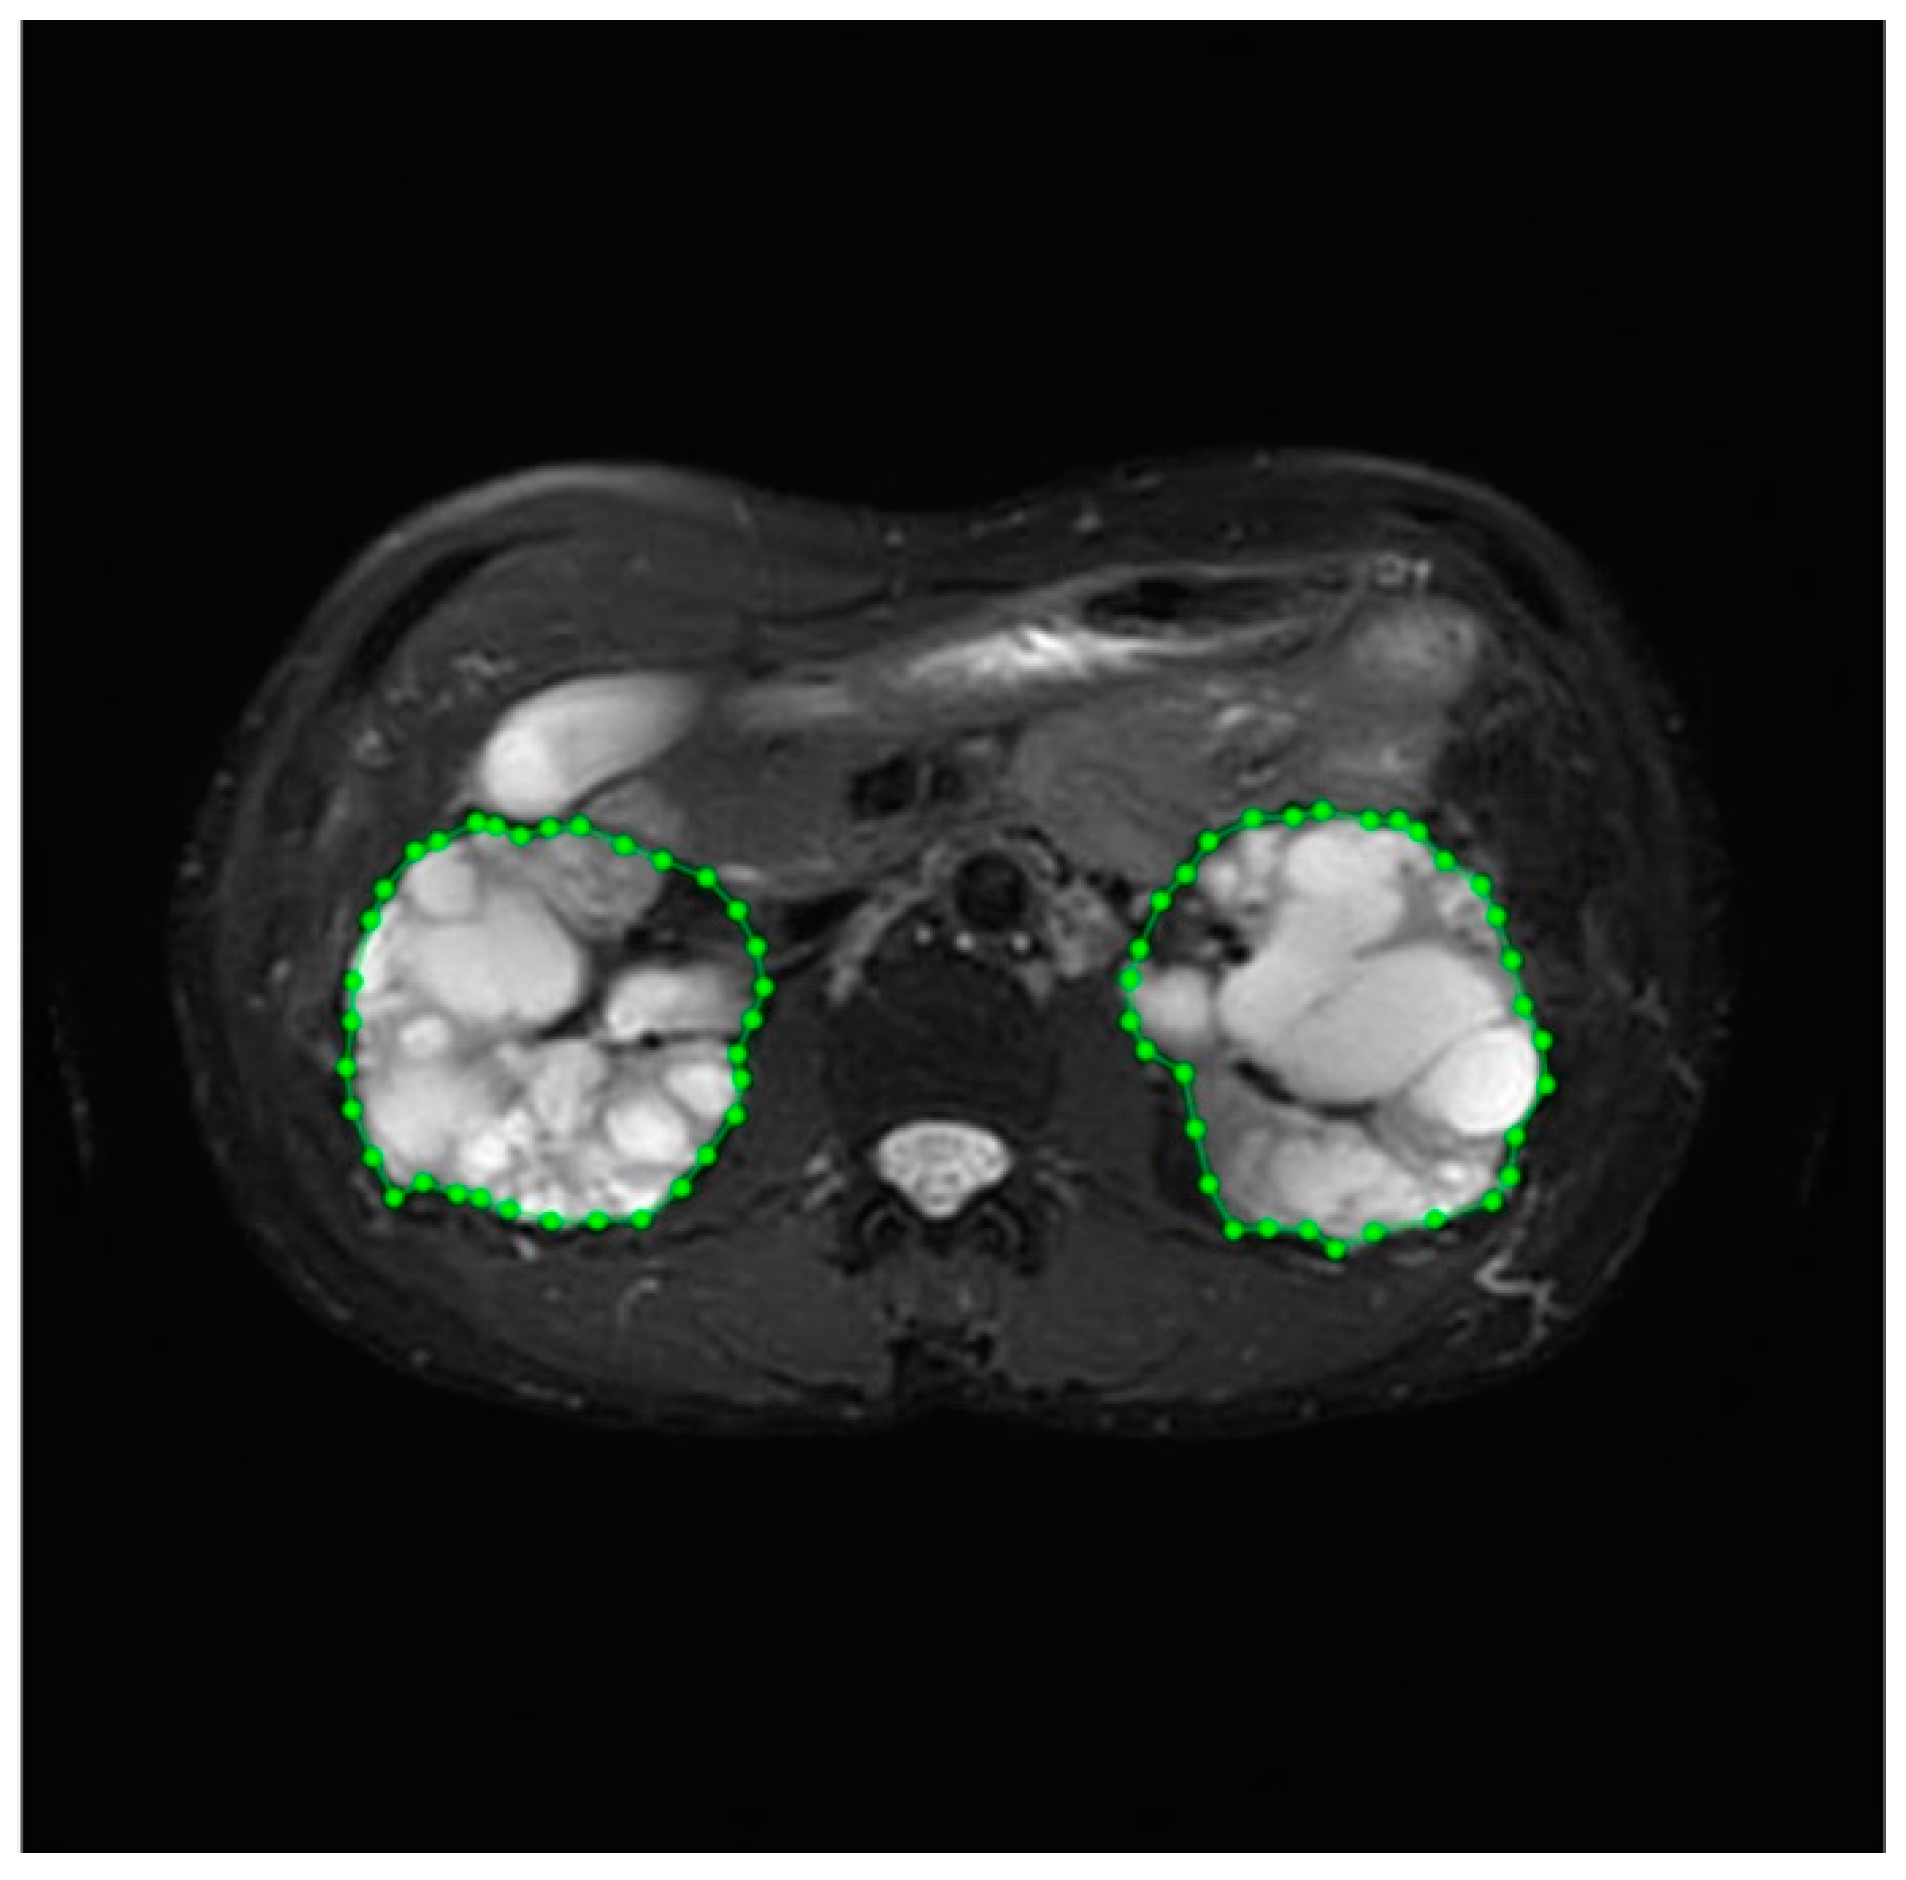

2.4. Data Labeling and Management

3.3. Accuracy of Segmentation